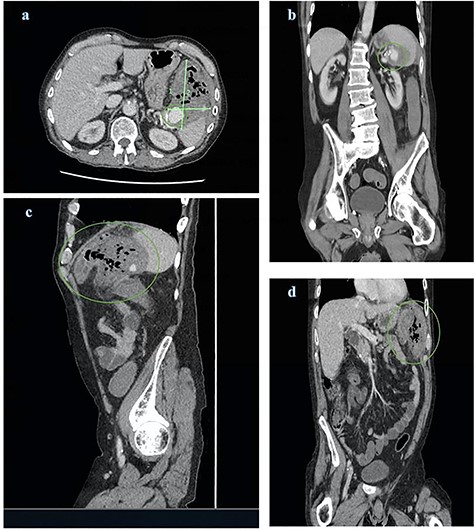

CT abdomen and pelvis views of the known splenic artery pseudoaneurysm with intravenous contrast (a) and (b) surrounded by a large inflammatory mass (a), (c) and (d); the mass demonstrates multiple foci of air and is intimately related to the splenic flexure

Computed tomography (CT) of abdomen and pelvis with contrast was ordered demonstrating a large peri-splenic mass with multiple foci of air (Fig. 1). The splenic flexure appeared to communicate with the mass via the posterior wall indicative of an SAP erosion through the large bowel. The patient was taken for an emergency laparotomy with left hemicolectomy and splenectomy. The postoperative course was complicated by severe malnutrition related to chronic alcoholism and hospital acquired pneumonia resulting in sepsis unresponsive to antimicrobials. The patient requested palliation and died 3 weeks after initial presentation.